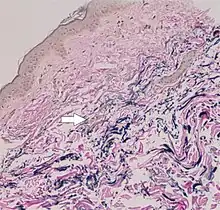

The diagnostic criteria for PXE are the typical skin biopsy appearance and the presence of angioid streaks in the retina. Criteria were established by consensus of clinicians and researchers at the 2010 biennial research meeting of the PXE Research Consortium.[32] and confirmed at the 2014 meeting[33] These consensus criteria state that definitive PXE is characterized by two pathogenic mutations in the ABCC6 or ocular findings – angioid streaks > 1 DD or peau d'orange in an individual <20 years of age together with skin findings:

- Diagnostic histopathological changes in lesional skin: Calcified elastic fibers in the mid and lower dermis, confirmed by positive calcium stain

| Pseudoxanthoma elasticum | LM: Mid-dermal calcification and fragmentation of elastic fibers EM: Mineralization in elastic fiber core |